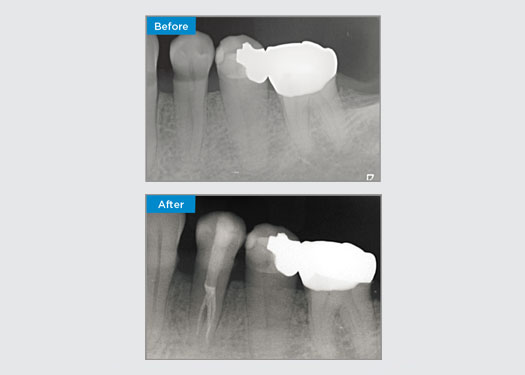

Het is vrij gebruikelijk om scheuren en breuken waar te nemen die verband houden met amalgaamrestauraties, vooral omdat ze groter worden omdat het “ongebonden” restauraties zijn. Veel van deze tanden zijn structureel aangetast en een zelfklevende, biomimetische aanpak is de ideale methode om deze tanden te herstellen. In het kader van een uitgebreider behandelplan is gepland dat dit kwadrant twee indirecte keramische onlays krijgt. De eerste en tweede molaren werden bij één bezoek gerestaureerd met CEREC Tessera, een geavanceerd lithiumdisilicaat.

Dr. Yo-Han Choi, Sydney, Australië